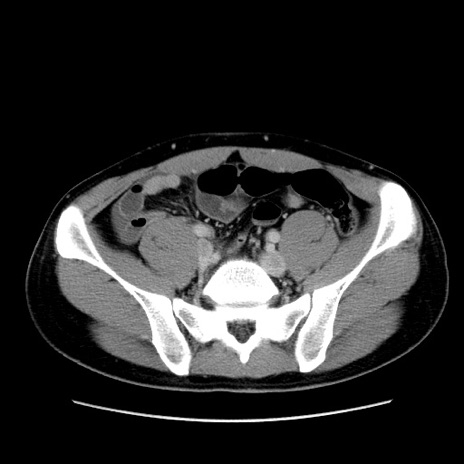

症例36(横断像)

【症例】20歳代 男性

【主訴】心窩部痛

【現病歴】今朝より上腹部痛あり。一旦軽快していたが再度出現したため救急要請。昨日夕に白身の魚を含む刺身を食べた。

【身体所見】BP 136/89mmHg、HR 74/min、BT 37.0℃、腹部:膨満、軟、心窩部に圧痛あり。反跳痛なし、筋性防御なし、腸雑音やや亢進あり。

【データ】WBC 17700、CRP 0.48